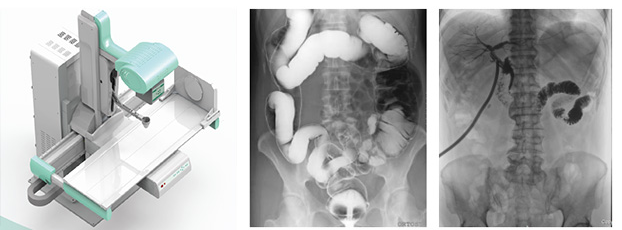

医用DR,以其高质量图像和高工作效率正逐渐替代现在传统X线摄影技术, 成为当今数字X线摄影技术的代表,它可以对于人体内部组织进行透视、检查,从而快速诊断患病情况,及时给予治疗。作为一种全新X线成像技术,医用DR使整个放射科特别是常规放射诊断的工作效率和经济效益得到明显提高。

医用DR是临床应用比较多见的放射科设备之一,其利用X射线对物体的穿透性原理,控制X射线用于对人体组织放射检查和放射治疗。如果您想购买普爱医疗的医用DR,或了解产品具体参数,欢迎联系我们。